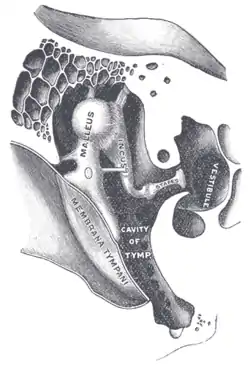

| Chain of ossicles and their ligaments. (Stapes visible near center right.) | |